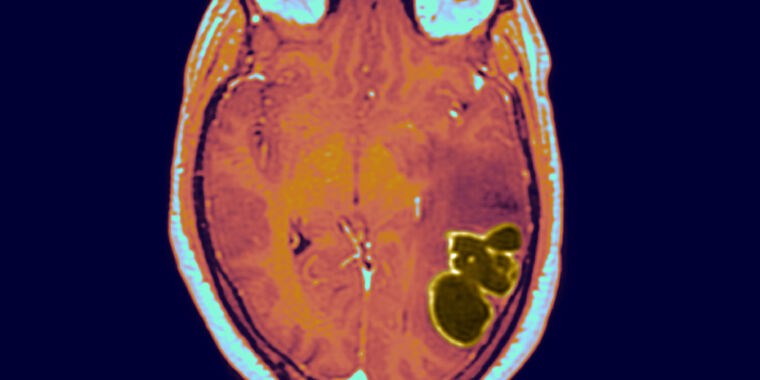

Cases of brain abscesses in American children have surged to new heights following the easing of pandemic restrictions, according to reports from the CDC. These abscesses, which are relatively rare but dangerous, are typically caused by bacteria or fungi entering the brain through respiratory infections such as COVID-19, the flu, or sinusitis. The CDC emphasizes the importance of children staying up-to-date with their vaccinations to prevent these infections. While cases have fallen since a peak in December 2022, they remain above the baseline maximum, indicating the need for continued monitoring and vigilance.